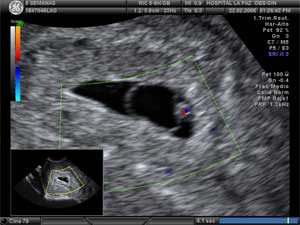

Embrión de dos semanas en ecografía Doppler

En esta ecografía 2D se aprecia un embrión de 2 milímetros y 5,2 semanas de gestación. La ecografía Doppler color puede ayudarnos a apreciar con mayor claridad la vitalidad del embrión. Las manchas de color rojo y azul ponen en evidencia el latido cardiaco; lo que se colorea es la sangre en movimiento.